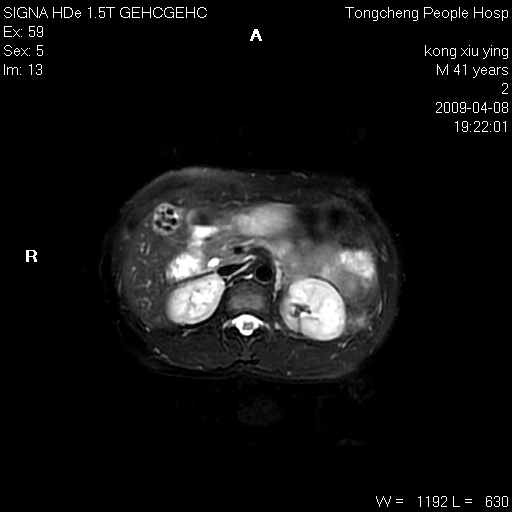

标题: CL1008:【经典】胆囊石榴籽样结石。 [打印本页]

标题: CL1008:【经典】胆囊石榴籽样结石。

女,41岁。健康体检——彩超提示:胆囊显示不清。平素健康,无不适感。

腹部mr扫描及mrcp,图像如下: